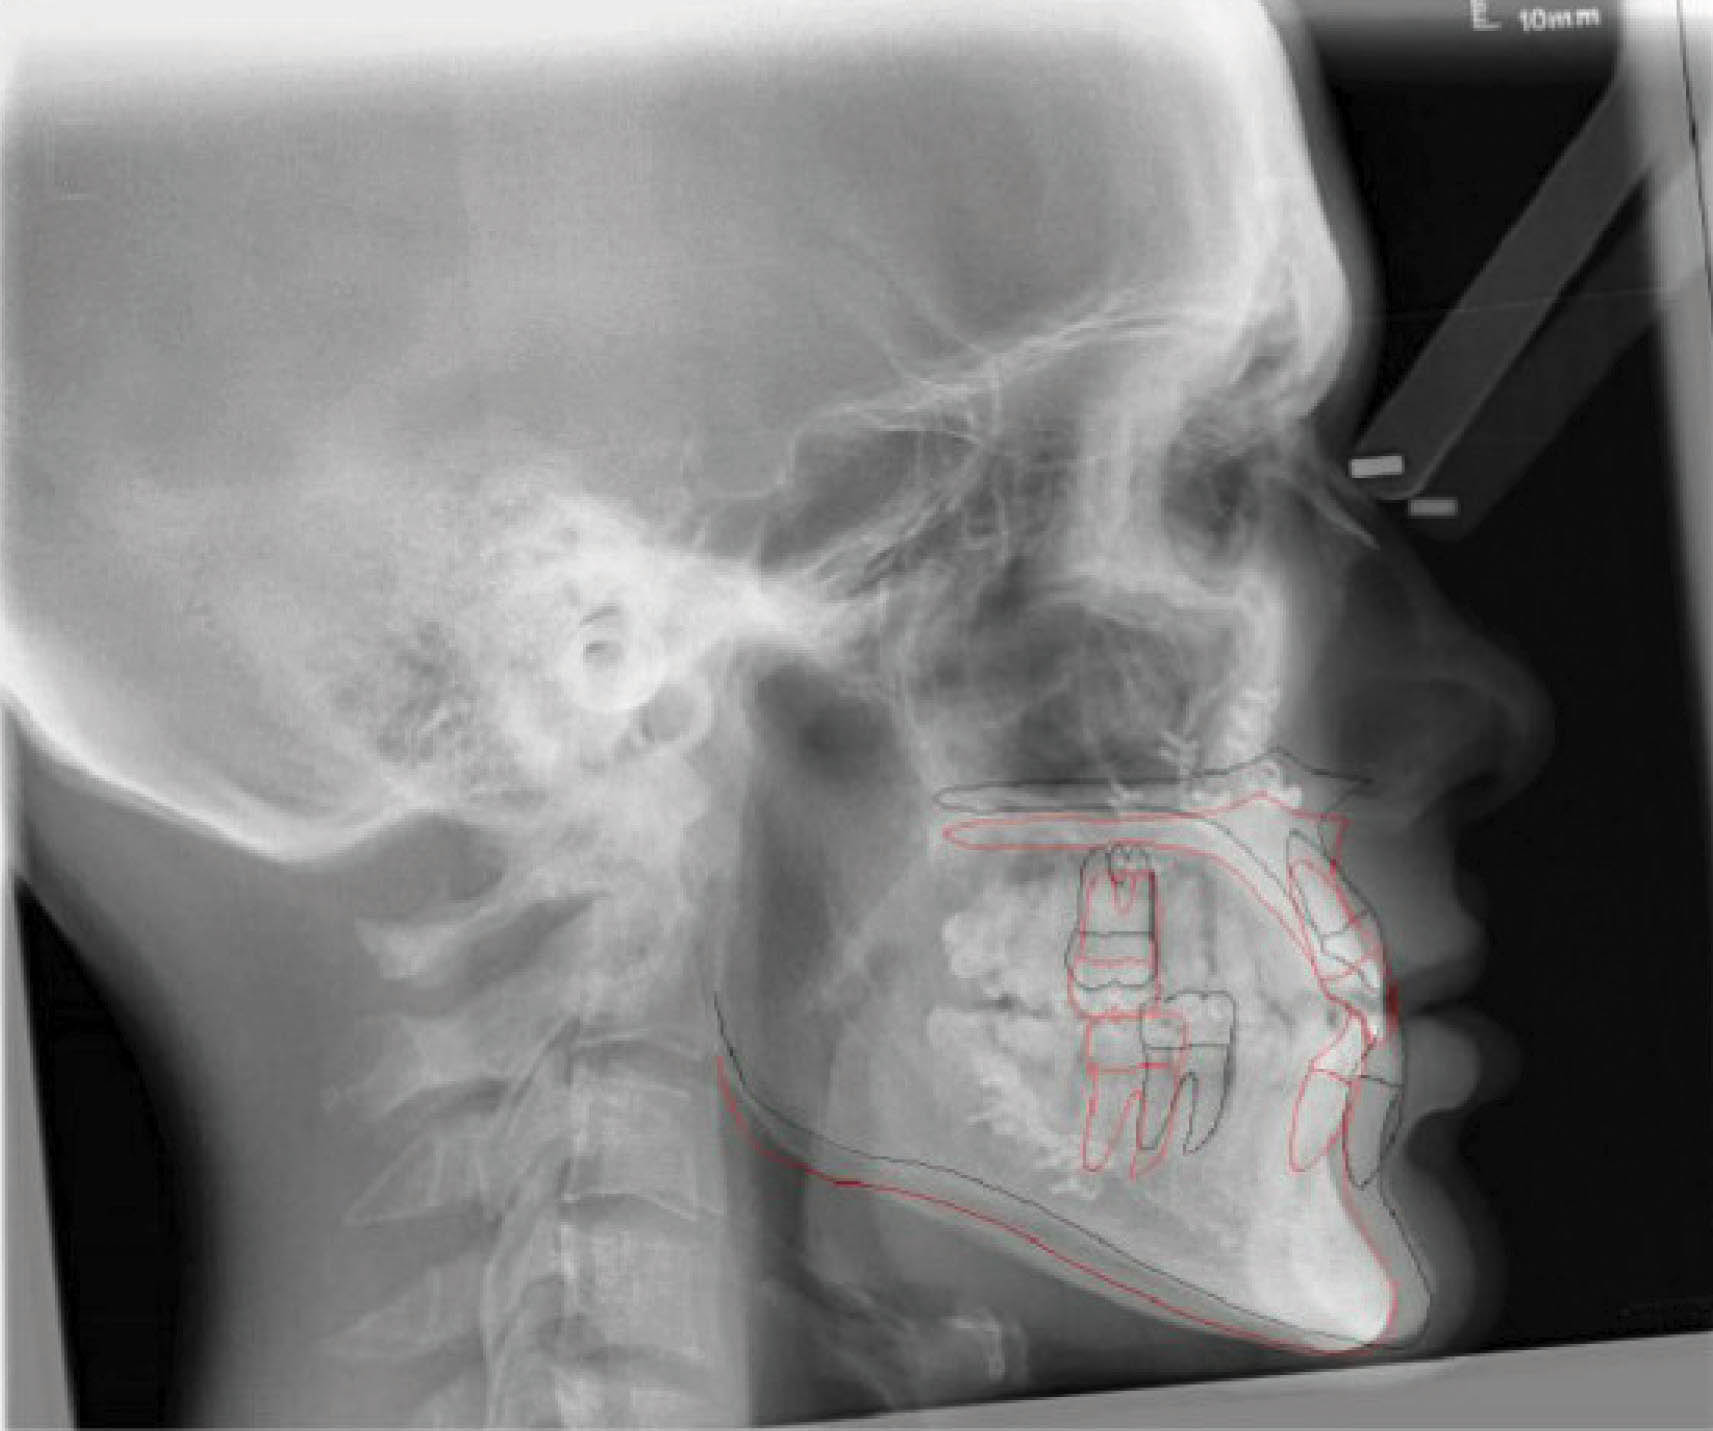

بیمار بعدی یک دختر ۱۶ ساله ClII/1 با اوربایت نرمال و اورجت زیاد است. کرادینگ مختصر دو فک دارد، قوس بالا تنگ، و پروفایل او طبیعی است (شکل 83-۶ الی 85-۶). در این بیمار از الاستیک کلاسII استفاده شده است. الگو اسکلتی طبیعی، رادیوگرافی لترال سفالومتری نشان دهنده دندانهای قدامی پروترود شده بالا با الگو طبیعی اسکلتی میباشد. رادیوگرافی OPG طبیعی است. قسمت بعُد افقی چک لیست را به این نحوه پر کردیم:

شکل 83-6

شکل 84-6

شکل 85-6